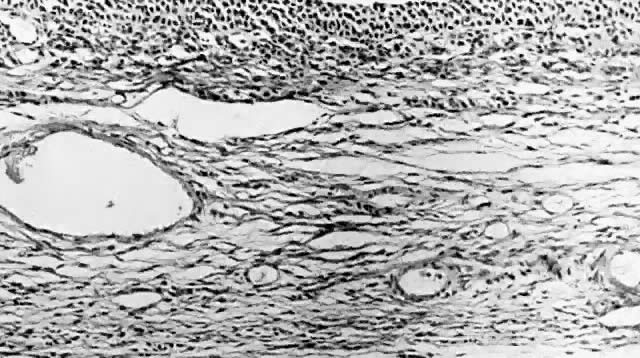

Benign cystic teratomas are quite common. They represent 70% of benign ovarian neoplasms in women up to age 40.9 Between age 40 and 50, they represent 40%; between age 50 and 60, they represent 20%. They comprise 15% of benign ovarian tumors in the seventh decade of life. They commonly consist primarily of ectoderm and mesoderm. The stratified squamous epithelium of the skin, its appendages, and neural tissue are the most common ectodermal derivatives (Fig. 2). The mesoderm is routinely represented by dermal connective tissue, but cartilage, bone, and muscle are also seen. The endoderm is represented by respiratory epithelium or gastrointestinal tract epithelium. However, endodermal derivatives are less commonly seen than the other types of tissue. This scarcity of endodermal derivatives is curious and of particular interest, because mesodermal induction in vertebrate embryos requires endoderm.23 Thyroid, another endodermal tissue, is present with some frequency. When it represents a significant component of the tumor. the term struma ovarii is used. Strumas occur in slightly older women than is usual for benign cystic teratomas. If the tissue functions autonomously, then clinical thyroid disease may occur. The carcinoid syndrome may also have its origin in typical carcinoids arising in benign cystic teratomas.

Fig. 2. Benign cystic teratoma. Cyst lining composed of keratinizing squamous epithelium with sebaceous glands, smooth muscle, and sweat glands in the wall (hematoxylin and eosin stain, x60).